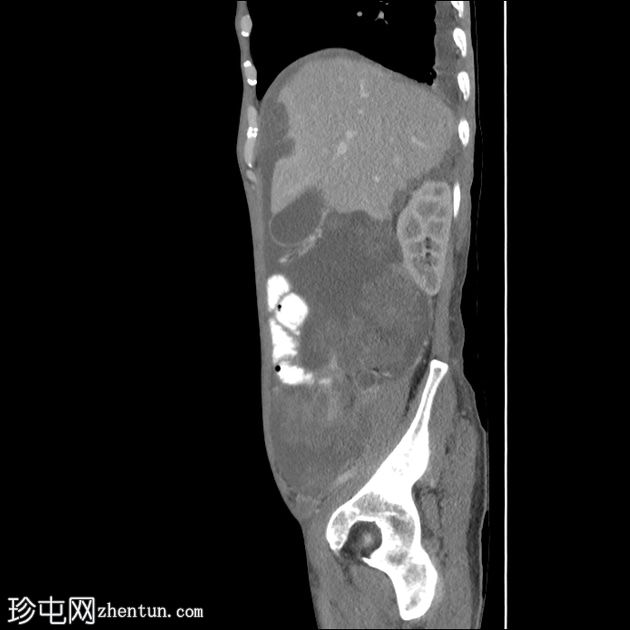

轴位增强扫描(门静脉期)

大网膜和肠系膜内可见低密度、不均匀的腹膜积液,脏器表面呈扇形凹陷,尤其以肝脏和脾脏最为明显。

阑尾肿大,长 5.0 cm,直径 1.2 cm,大小符合,可能提示阑尾黏液性肿瘤

直肠穹窿可见一处厚度 1.2 cm、长 4.0 cm 的增强壁增厚。可见病灶周围及骶前淋巴结肿大,最大者直径 1.6 cm。

左下腹可见末端结肠造口。